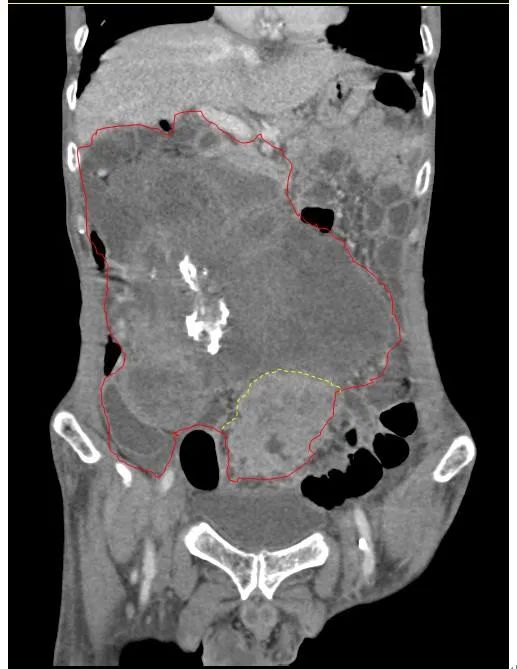

患者王大爷,男,72岁,发现腹腔肿物10余年,近两年来患者双下肢乏力、贫血,依靠间断输血维持着正常生活,出现头昏,行动困难,腹部疼痛及便血慕名来我院就诊。入院后查体评估患者年龄大,体质差,严重贫血,肺部感染及肠梗阻征象,腹部增强CT检查提示腹膜后巨大肿瘤,长径超过30厘米,占据大部分腹腔,并可能存在双原发肿瘤。

苗满园肿瘤外科团队在麻醉科/手术室的紧密配合下为该患者进行手术,术中发现肿瘤巨大,几乎占据了整个腹腔,从左侧向右腹腔延伸,向上将肝、肾挤向膈下,向左将胃及小肠挤向左上腹,向下深达盆腔内,包绕下腔静脉、肠系膜上动脉等大血管及输尿管,回盲部及回肠也受侵犯。手术难度巨大,风险极高。团队凭借着高超的手术技能和精准的手术预案沉着应对,迎难而上,应用高频电刀、超声刀、切割缝合器等先进设备,耗时近5小时为患者切除了巨大腹腔肿瘤,并联合右半结肠切除,术中出血仅50ml。术后病理为腹膜后巨大平滑肌瘤+回肠腺癌。